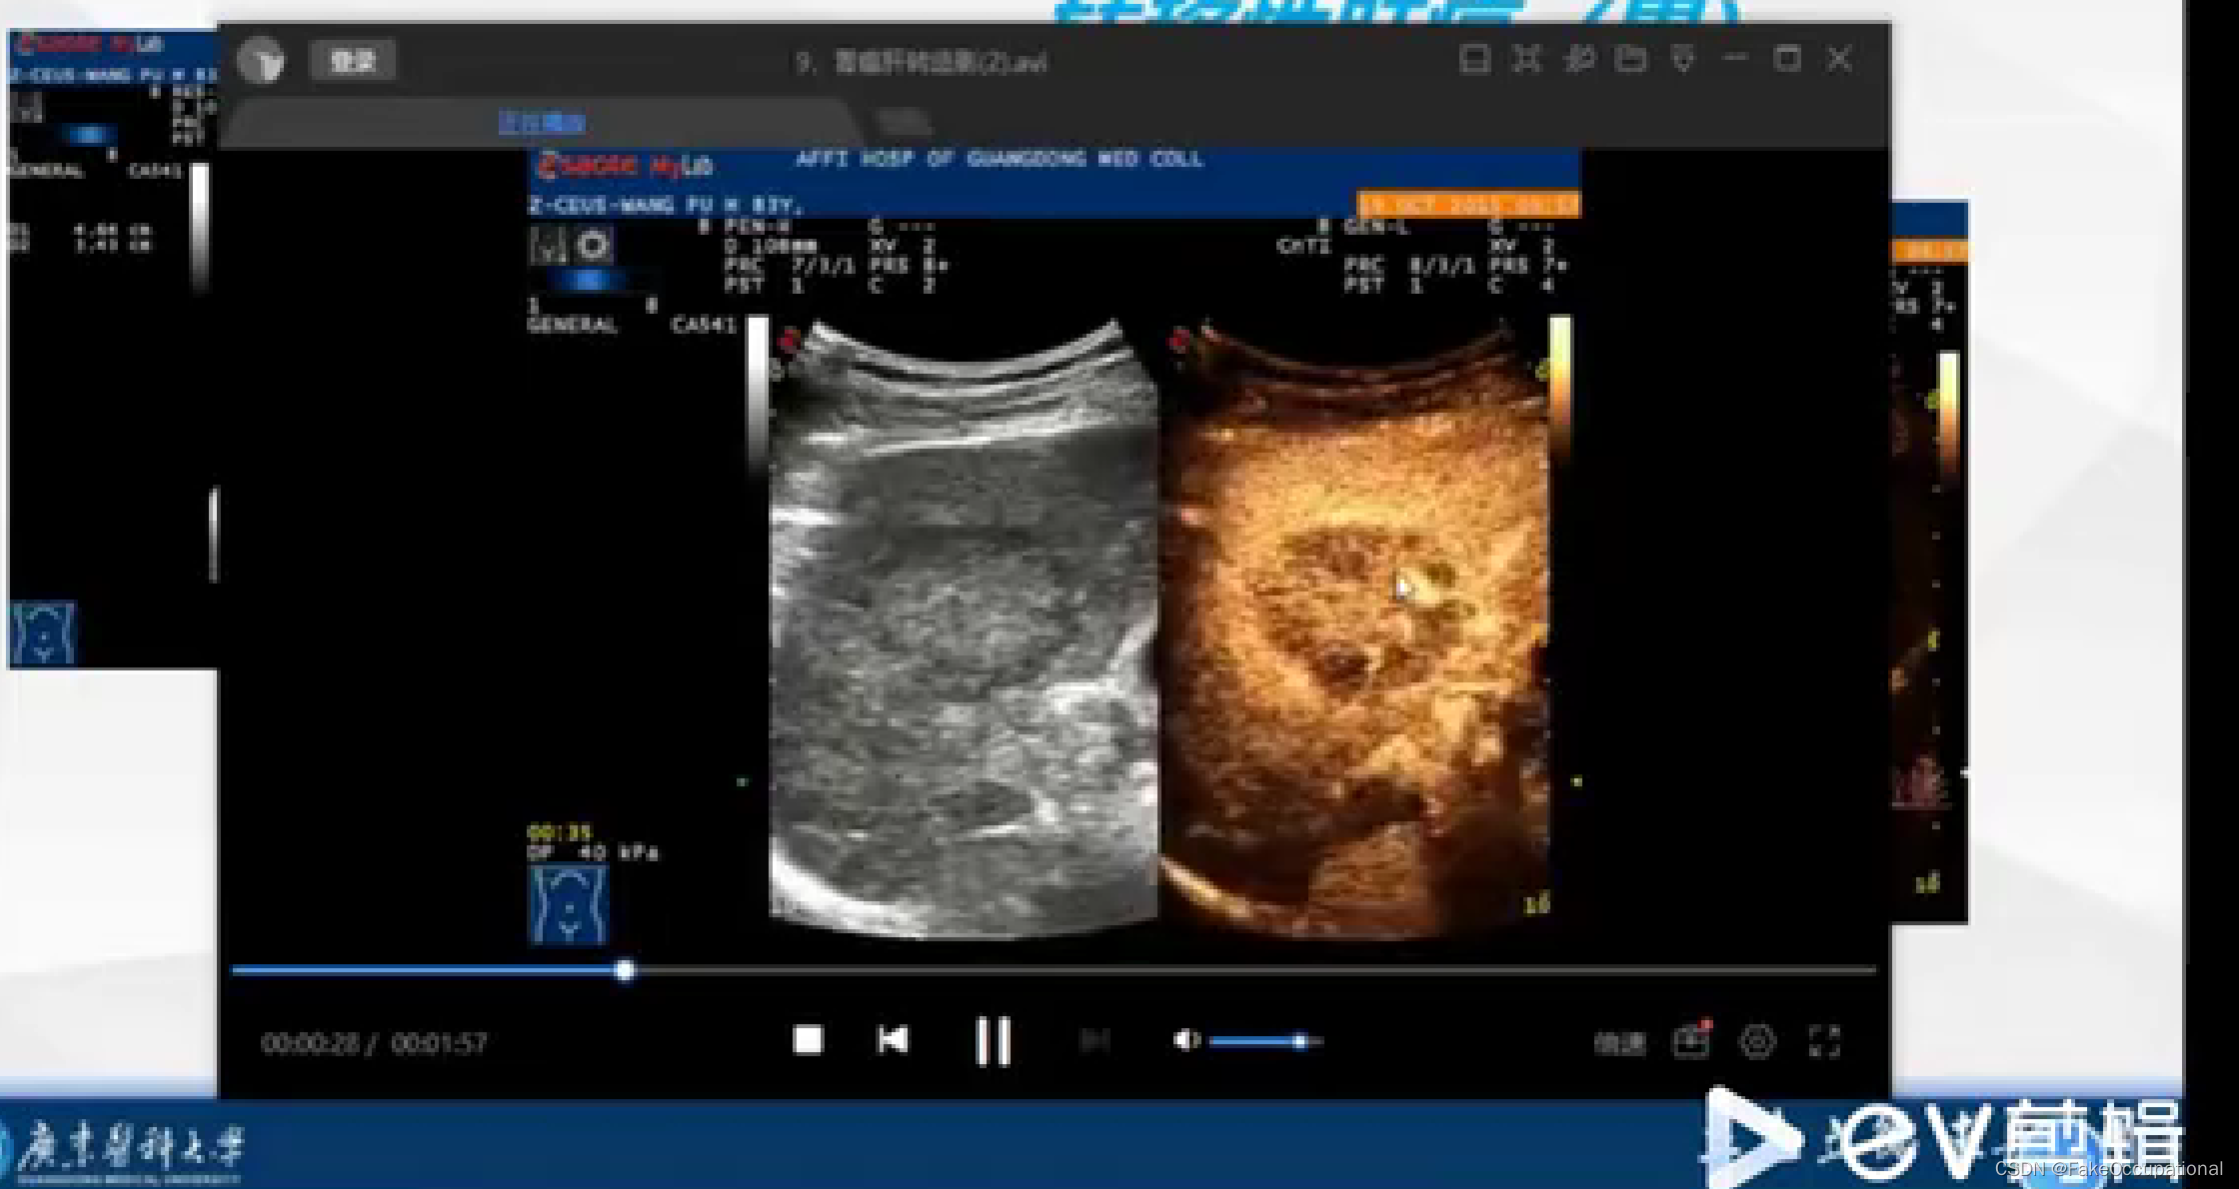

2.超声造影

- 超声更多起一个筛查的作用,定性需要造影或者其他设备的辅助

- 超声造影